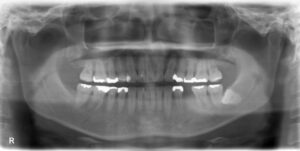

インプラント治療を成功させるうえで重要なのは、精密な治療計画です。そのためには顎の骨の状態を精密に把握する必要があります。そこで活躍するのが歯科用CTです。これまでのレントゲン検査とはくらべものにならないほどの詳細な情報を立体画像で確認することができます。

顎の骨の骨密度や厚み、さらに神経や血管の位置まで把握できるので、どの位置にどの角度でどれくらいの深さにどの種類のインプラントを埋入すればいいのかの綿密なシミュレーションが可能です。